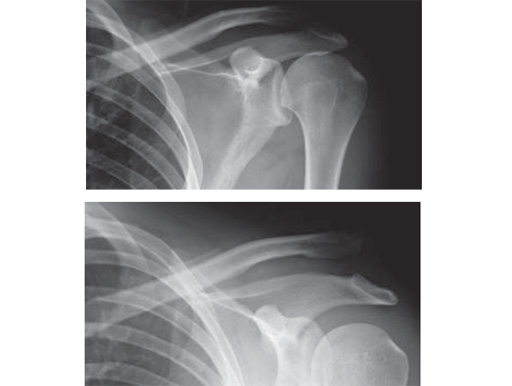

Fig.

Preoperative x-rays